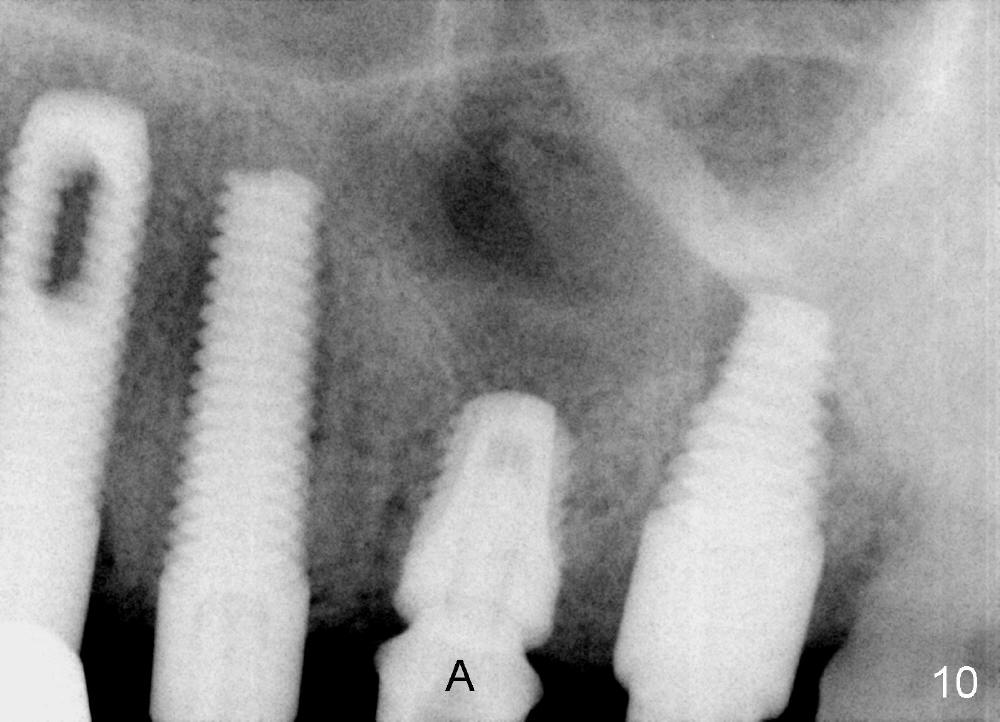

The provisional dislodges once more several days later.  The implant at the site of #14 is uncovered; an abutment (A) is placed (Fig.10.11); a provisional (Fig.12 P) 3-unit bridge is fabricated and cemented securely.  There is some occlusal contact with the opposing teeth.

In fact this senile patient unintentionally uses the provisional as a permanent restoration and chews bone on the left side, since at the same time implants at the sites of #29 and 30 are not restored.  Two and a half months post implantation at #13 and 15, the patient returns because the provisional has fractured (Fig.14), while all of the 3 implants are stable with sign of osteointegration (Fig.13).  The patient requests early final restoration, which is honored.  After fabrication of a new temporary bridge, he eats like a dog!